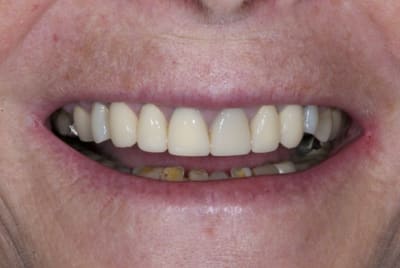

La suite avec les deuxièmes provisoires en places, le projet esthétique étant validé, les emp. ont été réalisées, ceramo-metal sur moignon composite a venir..